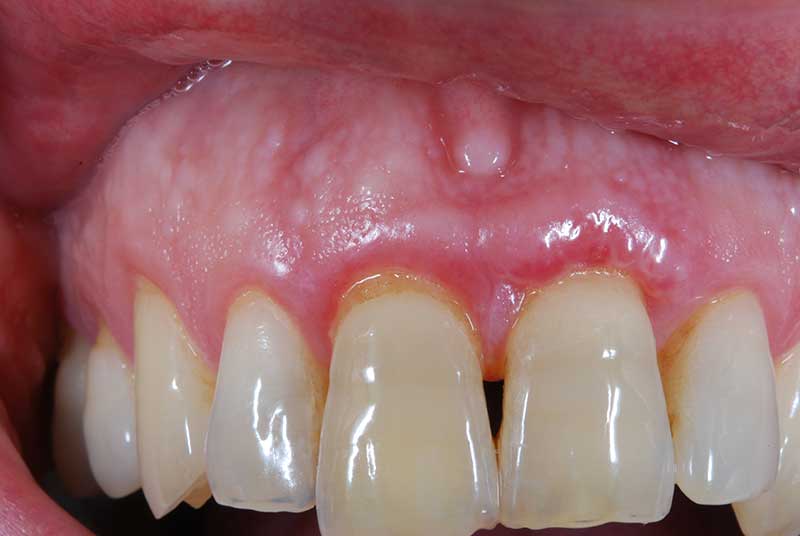

Lembo libero per correggere una recessione gengivale